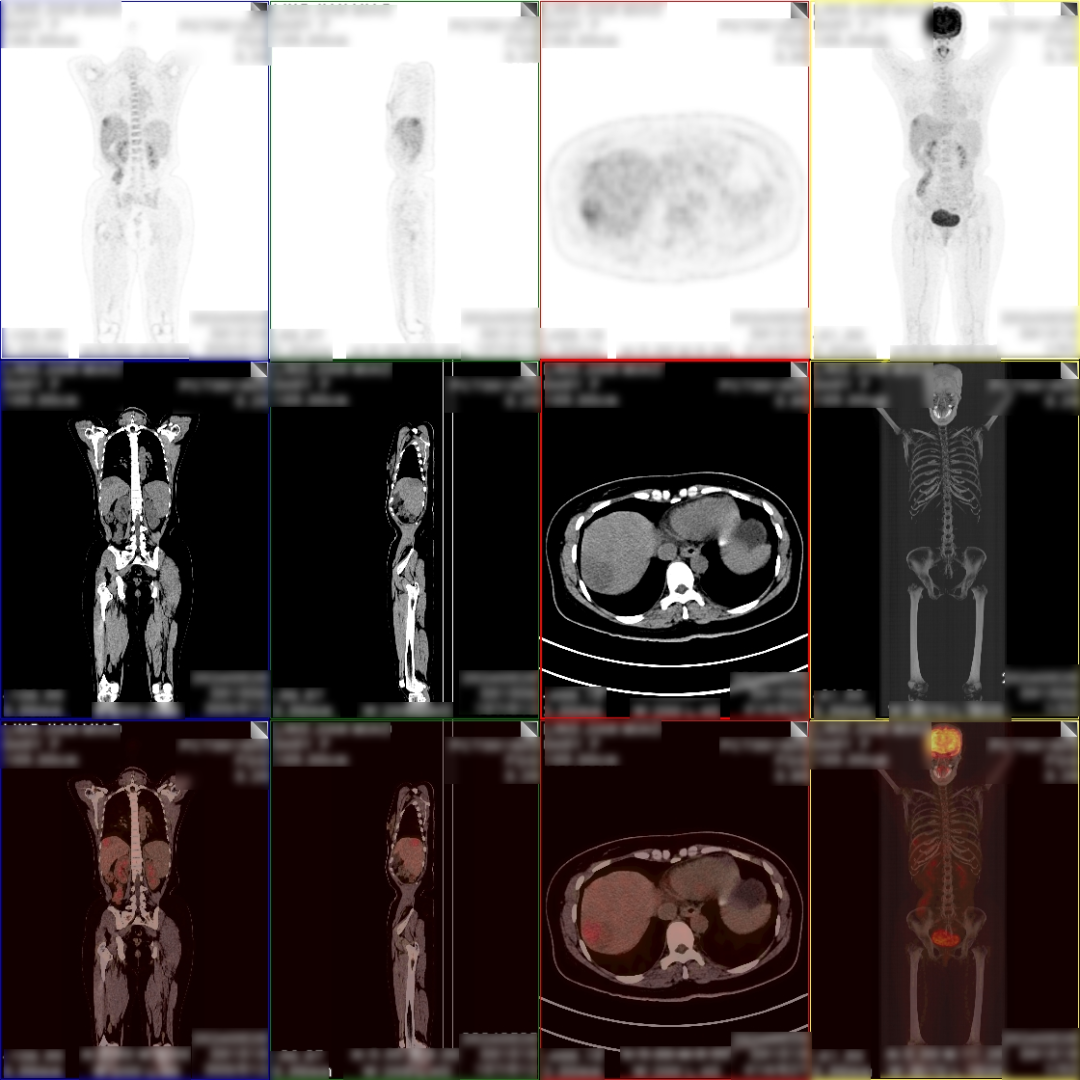

病史:女,48岁,无明显不适,健康查体,无特殊病史及手术史。乙肝大三阳,AFP:380.21ng/mL,CA199:33.24U/ml,CA125、CA153、CA724、 CEA(-)。

PET/CT检查所见

1、肝 S8 段见 1 个稍低密度软组织肿块,病灶内部分组织代谢增高,考虑肝细胞肝癌;

2、肝 S8 段另见 1 个稍低密度结节,代谢轻度增高,考虑为小肝癌或肝内子灶形成,该压迫相邻肝中静脉。

PET/CT活检病理:原发性肝癌